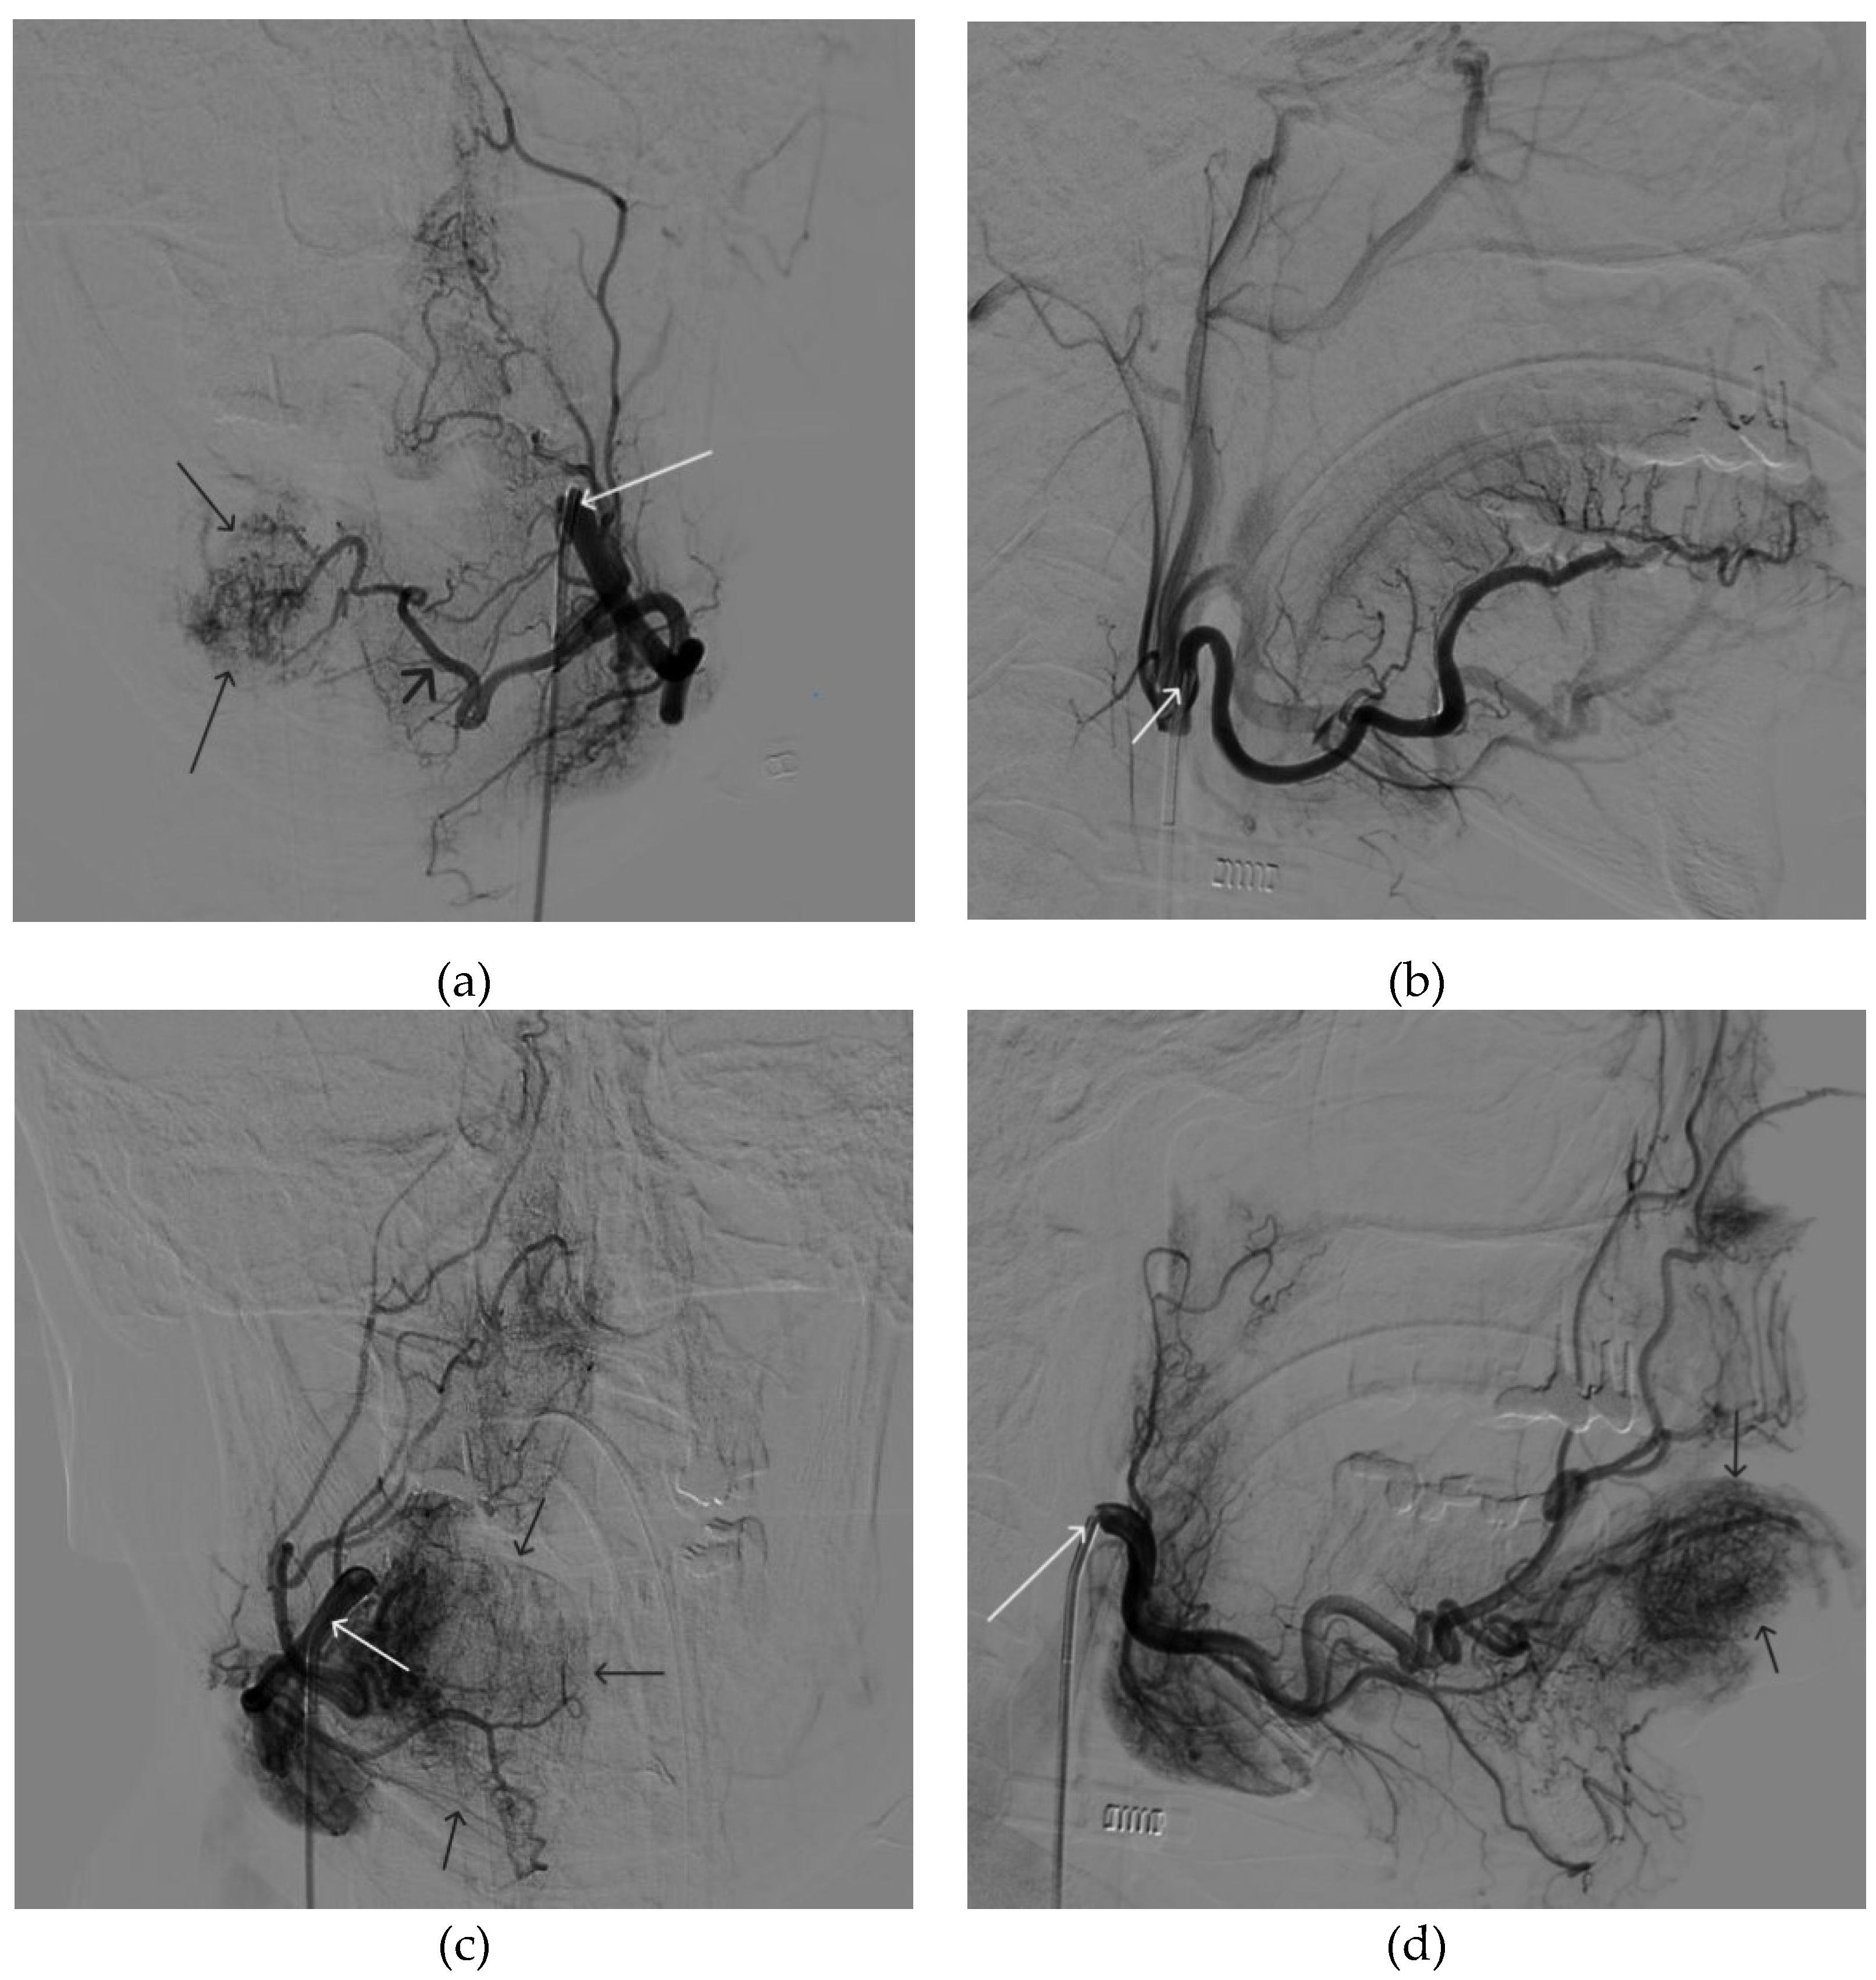

Figure 12. Distribution of Onyx-18 along the vascular network of the paraganglioma: a – direct projection, b - lateral projection (white arrows indicate filling of the vascular network of the paraganglioma, black arrows indicate an inflated balloon in the left internal carotid artery).

Figure 13. X-ray in single shot mode. a, b and c – demonstrate gradual spreading of Onyx-18 (NAGLEMs cast) through the vascular network of the paraganglioma direct projections (black arrows indicate filling of the vascular network of the paraganglioma, white arrows indicate an inflated balloon in the left internal carotid artery).

Figure 14. Digital subtraction angiography from the left common carotid artery: a – direct projection, b - lateral projection (white arrows indicate the guiding catheter in the left external carotid artery, black arrows indicate the boundaries of the embolized paraganglioma).